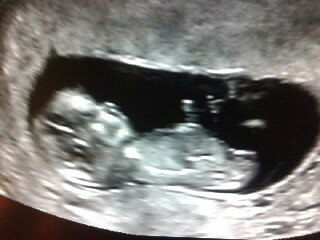

У некоторых узи такое не понятно на такой сроке, и думала так у всех. А у вас так хорошо, видно масюсю)))))) Здорово!!!! Так же хочу))